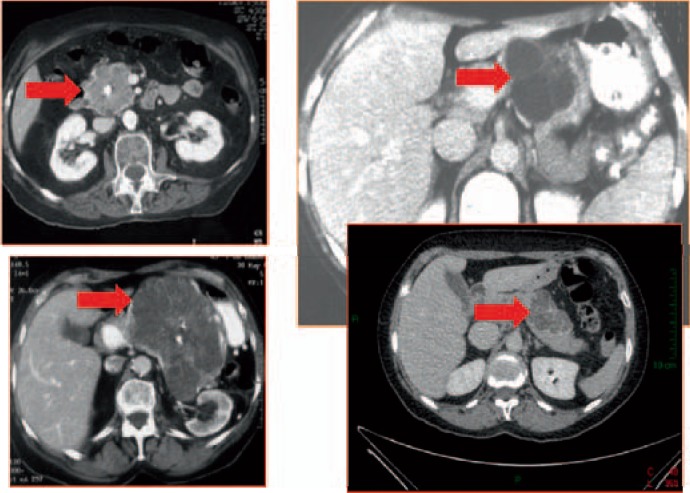

In most of the cases, SCN diagnosis is easy if multiple microcysts are seen on CT scan (honeycomb aspect) (fig. 4), MRI, or EUS. Some SCNs contain macrocysts; however, the visualization of a microcystic area is sufficient for diagnosis. Central calcifications may be present. The peripheral wall is thin (<2 mm) and nearly invisible on imaging procedures. SCN is a unique tumor except in patients with von Hippel-Lindau disease in which there are numerous SCNs, pancreatic neuroendocrine tumors, and simple cysts within the gland [14] (fig. 5).

Fig. 4.

CT scan showing four typical SCNs (red arrows) with (both left panels) or without central calcifications (image courtesy of Dr. Marie Pierre Vullierme, Hôpital Beaujon).